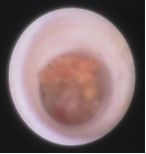

正常乳管

正常乳管管壁光滑呈乳白色或淡紅色,毛細血管清晰,彈性好,從主乳管遠端開始樹杈型的逐級分支。我們一般可以可見1~4級分支,分支開口處可見2~4個分叉口,常見為2支。